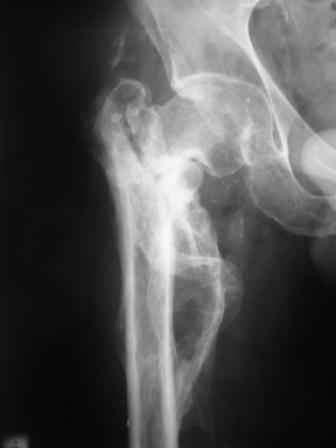

Больной Н. 44 года травма 1,5 года назад июнь 2008 года чрез-под вертельный перелом правого бедра. Во время лечения у больного развился алк. делирий, проводилось консервативное лечение перелома.

Беспокоят боли, укорочение конечности.Укорочение 3 см. Ногу поднимает, сгибание ограничено, ротационные движения в полном объеме.На КТ перелом сросся за счет костной мозоли.Что делать?

Уважаемый Глеб, боли из-за ложного сустава шейки бедра. Сращения там нет.

Уважаемый Глеб! Укорочение наверное побольше, да и наружно-ротационная установка скорее всего присутствует. Суставная щель прекрасная, головка живее всех живых. Ратую за подвертельную с латерализацией: исключает нарушение механической оси («исключает вальгус в коленe»), максимально удлиняет без натяжения m.iliacus. Для иллюстрации остеотомия-переделка (слава богу не автопеределка) у мужчины 65 лет.